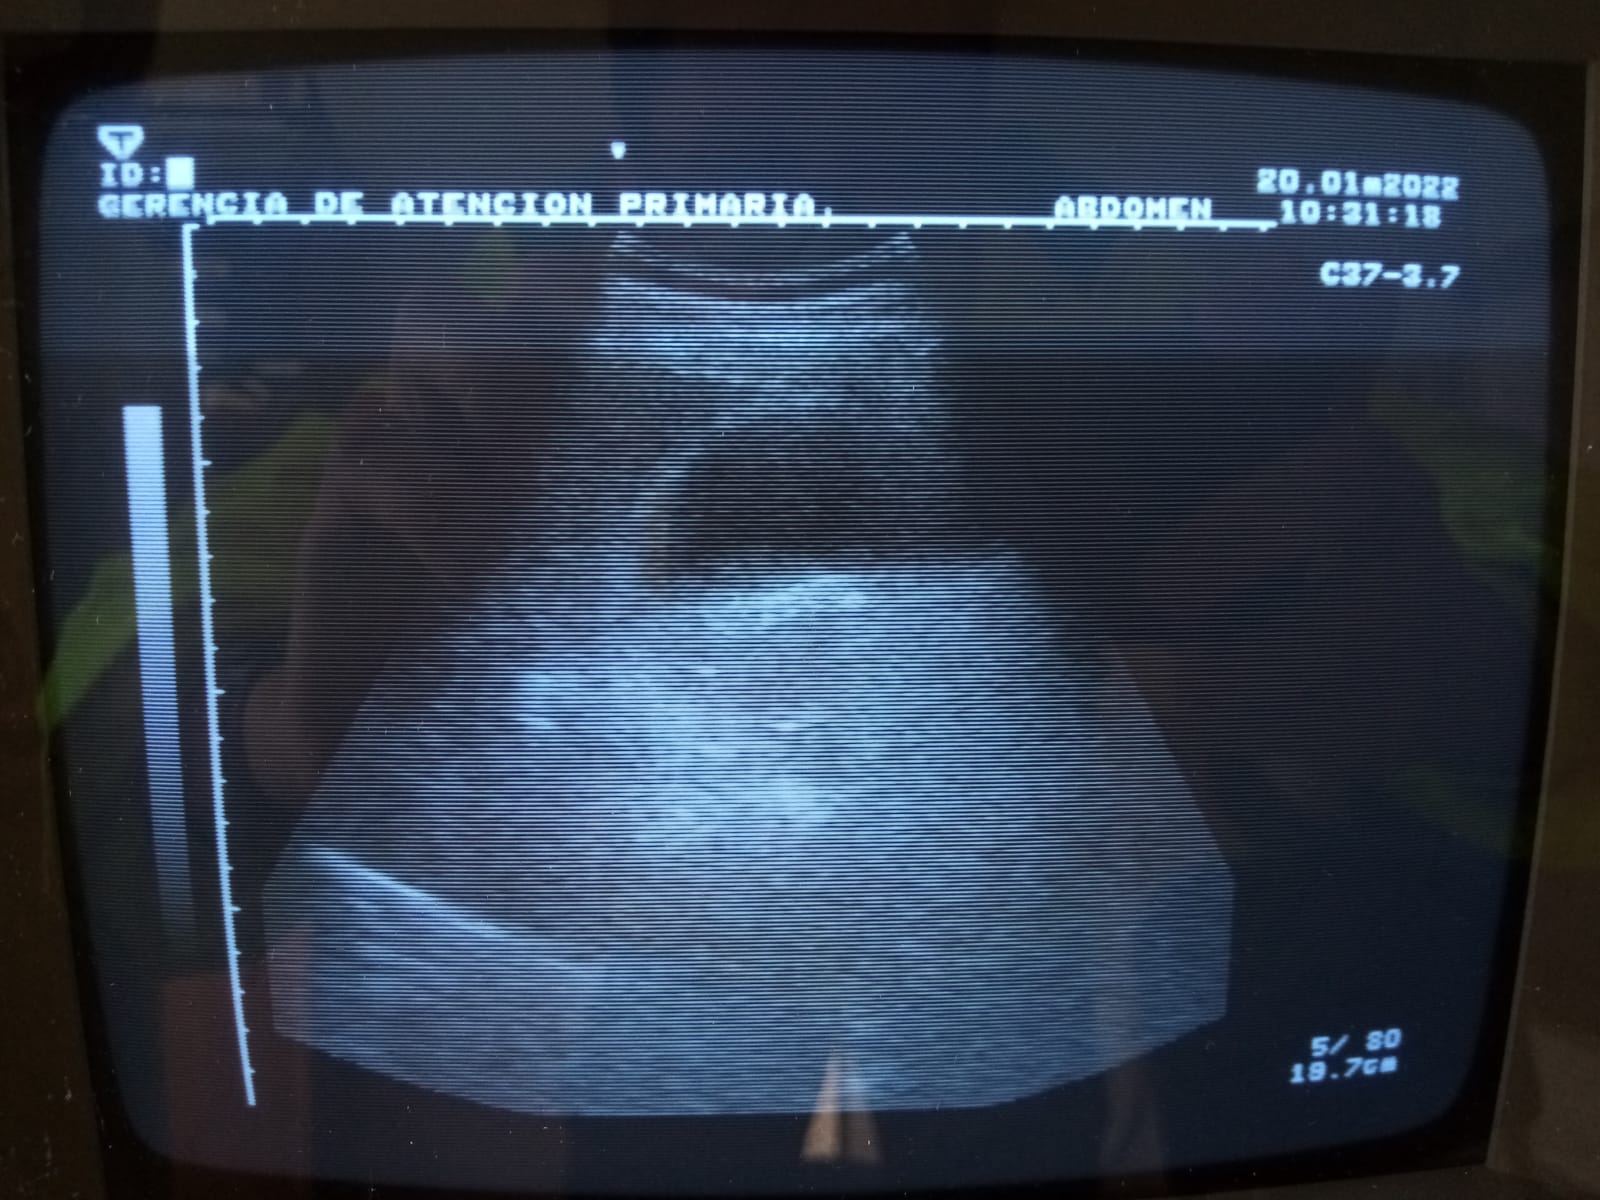

Vesícula biliar de tamaño conservado (38,5 mm), pared engrosada (6,7 mm), contenido biliar significativo, alitiásica.

Inicialmente sospecha de: crisis vertiginosa (exploración neurológica anodina), patología cardiaca (epigastralgia, nauseas en paciente diabético, electrocardiograma normal), cólico renal (tira de orina y puño-percusión renal negativas), cólico biliar (vesícula alitiásica)… Tras ecografía, pensamos en patologías que cursen con pared vesicular engrosada: colecistitis, adenomiomatosis, hepatitis, hipoproteinemia, cirrosis, ascitis, estado edematoso generalizado… Finalmente, nos decantamos por patología biliar complicada: colecistitis aguda.